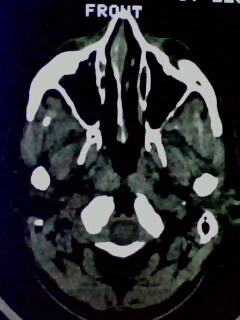

以下是引用随光逐影在2009-5-20 19:22:00的发言:[br]1)考虑左上颌骨近中线区含牙囊肿。2)鼻中隔右突偏曲。3)双侧下鼻甲肥大。